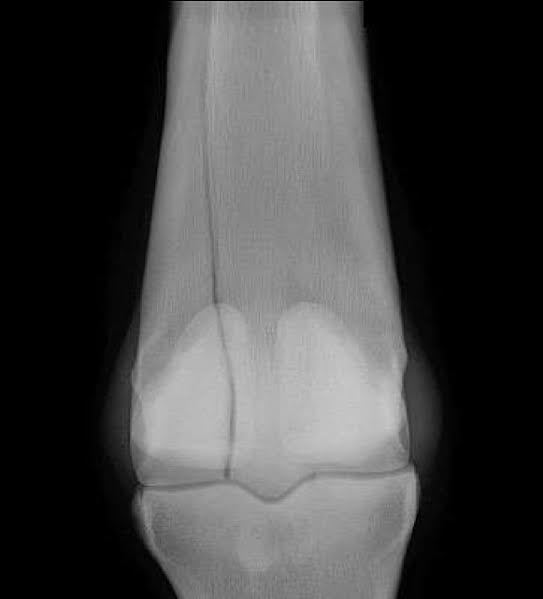

What is the most likely Dx?

A) fracture of the olecranon

B) radial nerve paralysis

C) septic arthritis of the elbow

D) osteochondrosis

E) none of the above